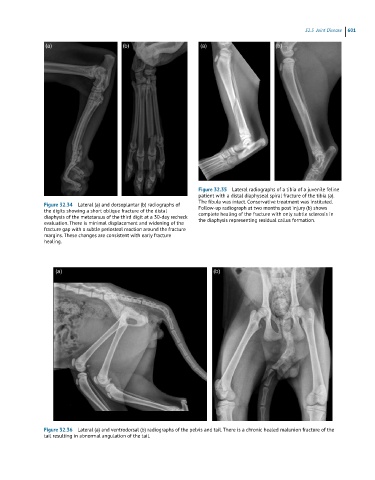

Figure 32.35 Lateral radiographs of a tibia of a juvenile feline

patient with a distal diaphyseal spiral fracture of the tibia (a).

The fibula was intact. Conservative treatment was instituted.

Figure 32.34 Lateral (a) and dorsoplantar (b) radiographs of Follow-up radiograph at two months post injury (b) shows

the digits showing a short oblique fracture of the distal complete healing of the fracture with only subtle sclerosis in

diaphysis of the metatarsus of the third digit at a 30-day recheck the diaphysis representing residual callus formation.

evaluation. There is minimal displacement and widening of the

fracture gap with a subtle periosteal reaction around the fracture

margins. These changes are consistent with early fracture

healing.

Figure 32.36 Lateral (a) and ventrodorsal (b) radiographs of the pelvis and tail. There is a chronic healed malunion fracture of the

tail resulting in abnormal angulation of the tail.